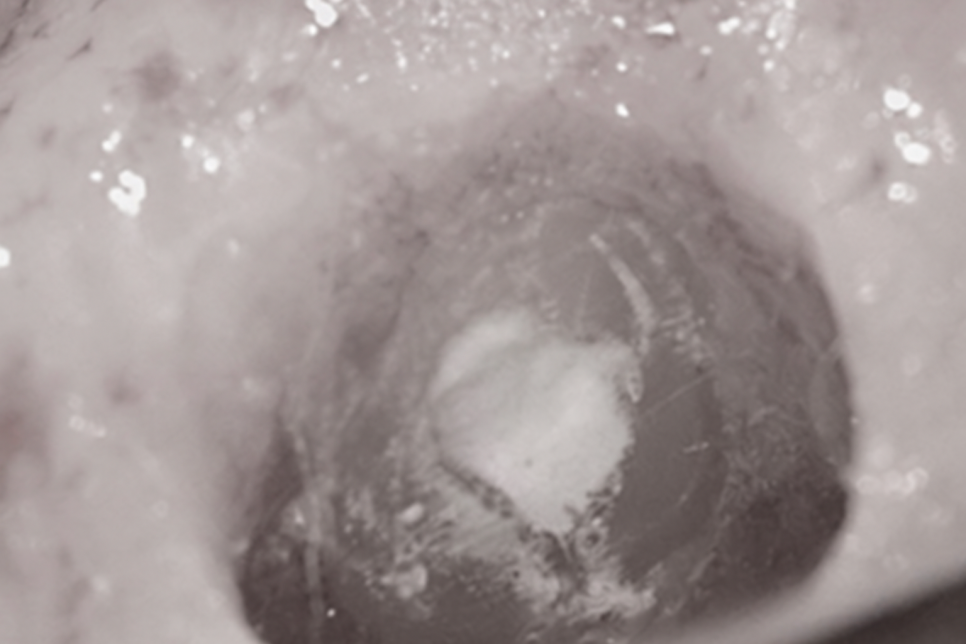

당산동 치과 사진을 보시면 내부 조직이 온전히 제거되어

재료가 채워져 있는 모습이 확인되고 있습니다.

이로써 일전에 신경치료를 받았음을

알 수 있는데 그 후 예후가 불량합니다.

뿌리 끝을 자세히 보시면 치아 주변으로

검게 투과 양상이 뚜렷하게 증가하고 있습니다.

염증이 생겨났기 때문에 검게 보이는 것인데

꽤 넓은 영역에 농덩어리가 생겨나

단순히 재신경치료에 들어간다 해서

긍정적인 차도를 이끌어내긴 어렵다 생각됩니다.

이런 케이스에 적용해 볼 수 있는 게

치근단절제술이랍니다.

외과적으로 뿌리 끝 3mm가량을

절제해 줌으로써 세균이 들어와 감염되는

통로 자체를 제거해 주는 것이죠.